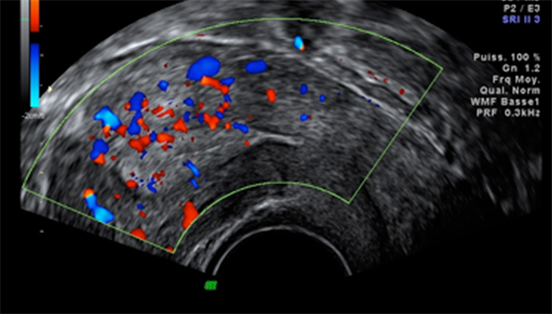

3.8. Distribution of Patients According to the Presence of Subendometrial Flow

Color Doppler ultrasound allows an assessment of endometrial receptivity in ART and in particular in in vitro fertilization, by visualizing the sub-endometrial flow (during the cycle, an invasion of the endometrium by small vessels from the myometrium is observed). The better the sub-endometrial flow, the better the endometrial receptivity.

This phenomenon was observed in 87% of our participants who became pregnant (Table 8). In our case, no link was found between the presence of sub-endometrial flow and the occurrence of pregnancy (p = 1). (Figure 4)

Figure 4. Pre-ovulatory sub-endometrial flow (D12).